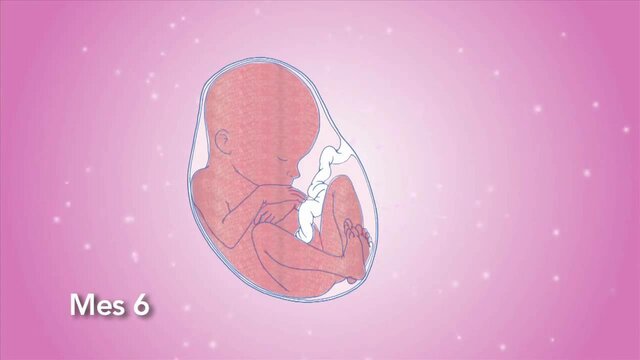

• SEXTO MES

SEXTO MES

Los bronquios y los pulmones casi han madurado. Aparecen

el pelo, las huellas dactilares y la gesticulación facial